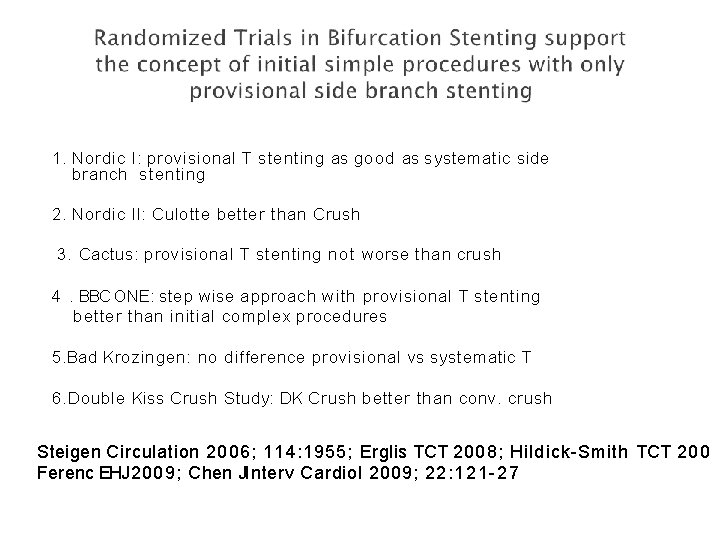

1. Nordic I: provisional T stenting as good as systematic side branch stenting 2. Nordic II: Culotte better than Crush 3. Cactus: provisional T stenting not worse than crush 4. BBC ONE: step wise approach with provisional T stenting better than initial complex procedures 5. Bad Krozingen: no difference provisional vs systematic T 6. Double Kiss Crush Study: DK Crush better than conv. crush Steigen Circulation 2006; 114: 1955; Erglis TCT 2008; Hildick-Smith TCT 200 Ferenc EHJ 2009; Chen JInterv Cardiol 2009; 22: 121 -27